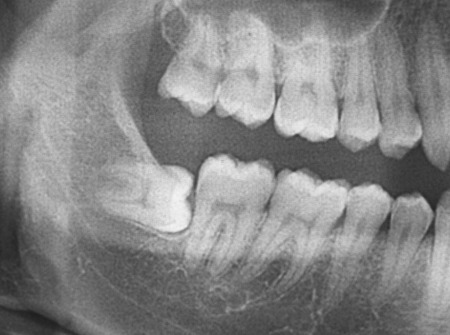

親知らずの抜歯で注意しないといけないのは、下顎の中に通っている大きな血管と神経を傷つけないようにしないといけません。神経を傷つけると麻痺が残ります。1~2ヶ月で消える事も有りますが、生涯消えない事もあります。

写真は神経の管に親知らずの根の先端が完全に入っている症例のCT画像です。